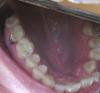

monozubik Опубликовано 23 марта, 2009 Поделиться Опубликовано 23 марта, 2009 (изменено) Около года назад на вышеуказанном зубе (семерка верхняя) был обнаружен пульпит. Зуб был депульпирован с последующей установкой пломбы (если не ошибаюсь филтек). На протяжении всего срока после лечения зуб меня больше не беспокоил. Два дня назад, во время еды, зуб сломался (( Раскололся он на две половинки. В результате одна половинка, более большая, статична, а другая шаталась. Доктором было принято решение удалить эту шатающуюся часть, чего и было проделано и я отправлен домой до нового визита к стоматологу. С оставшейся половиной будем решать что делать после заживления ранки. Примерно понимаю что вариантов два:* Удалить и установить имплант * Попытаться восстановить Почитав форум, возникли вопросы:1 Реально ли восстановить зуб без обтачивания соседних ? С сохранением ессно необходимой прочности.2 Уместен ли в сложившейся ситуации метод CEREC или всеж т.к. корень один удалили уже поздно реставрировать этим методом ? Реставрации CEREC прочны? 3 Если так и оставить, зуб сожрет кариес ? Или Кариес мертвичиной не питается ? Прокомментируйте пожалуйста, очень хочется услышать мнения нескольких специалистов дабы выбрать оптимальный метод лечения. Спасибо заранее за советы.Фотографии с цифровика прилагаю, пока они только такие. В следующий раз у доктора заберу ренгеновский. Изменено 23 марта, 2009 пользователем monozubik Ссылка на комментарий